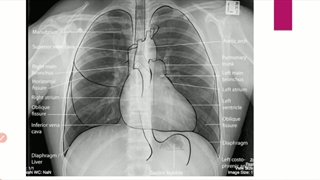

تنفس از طریق تراکئوتومی